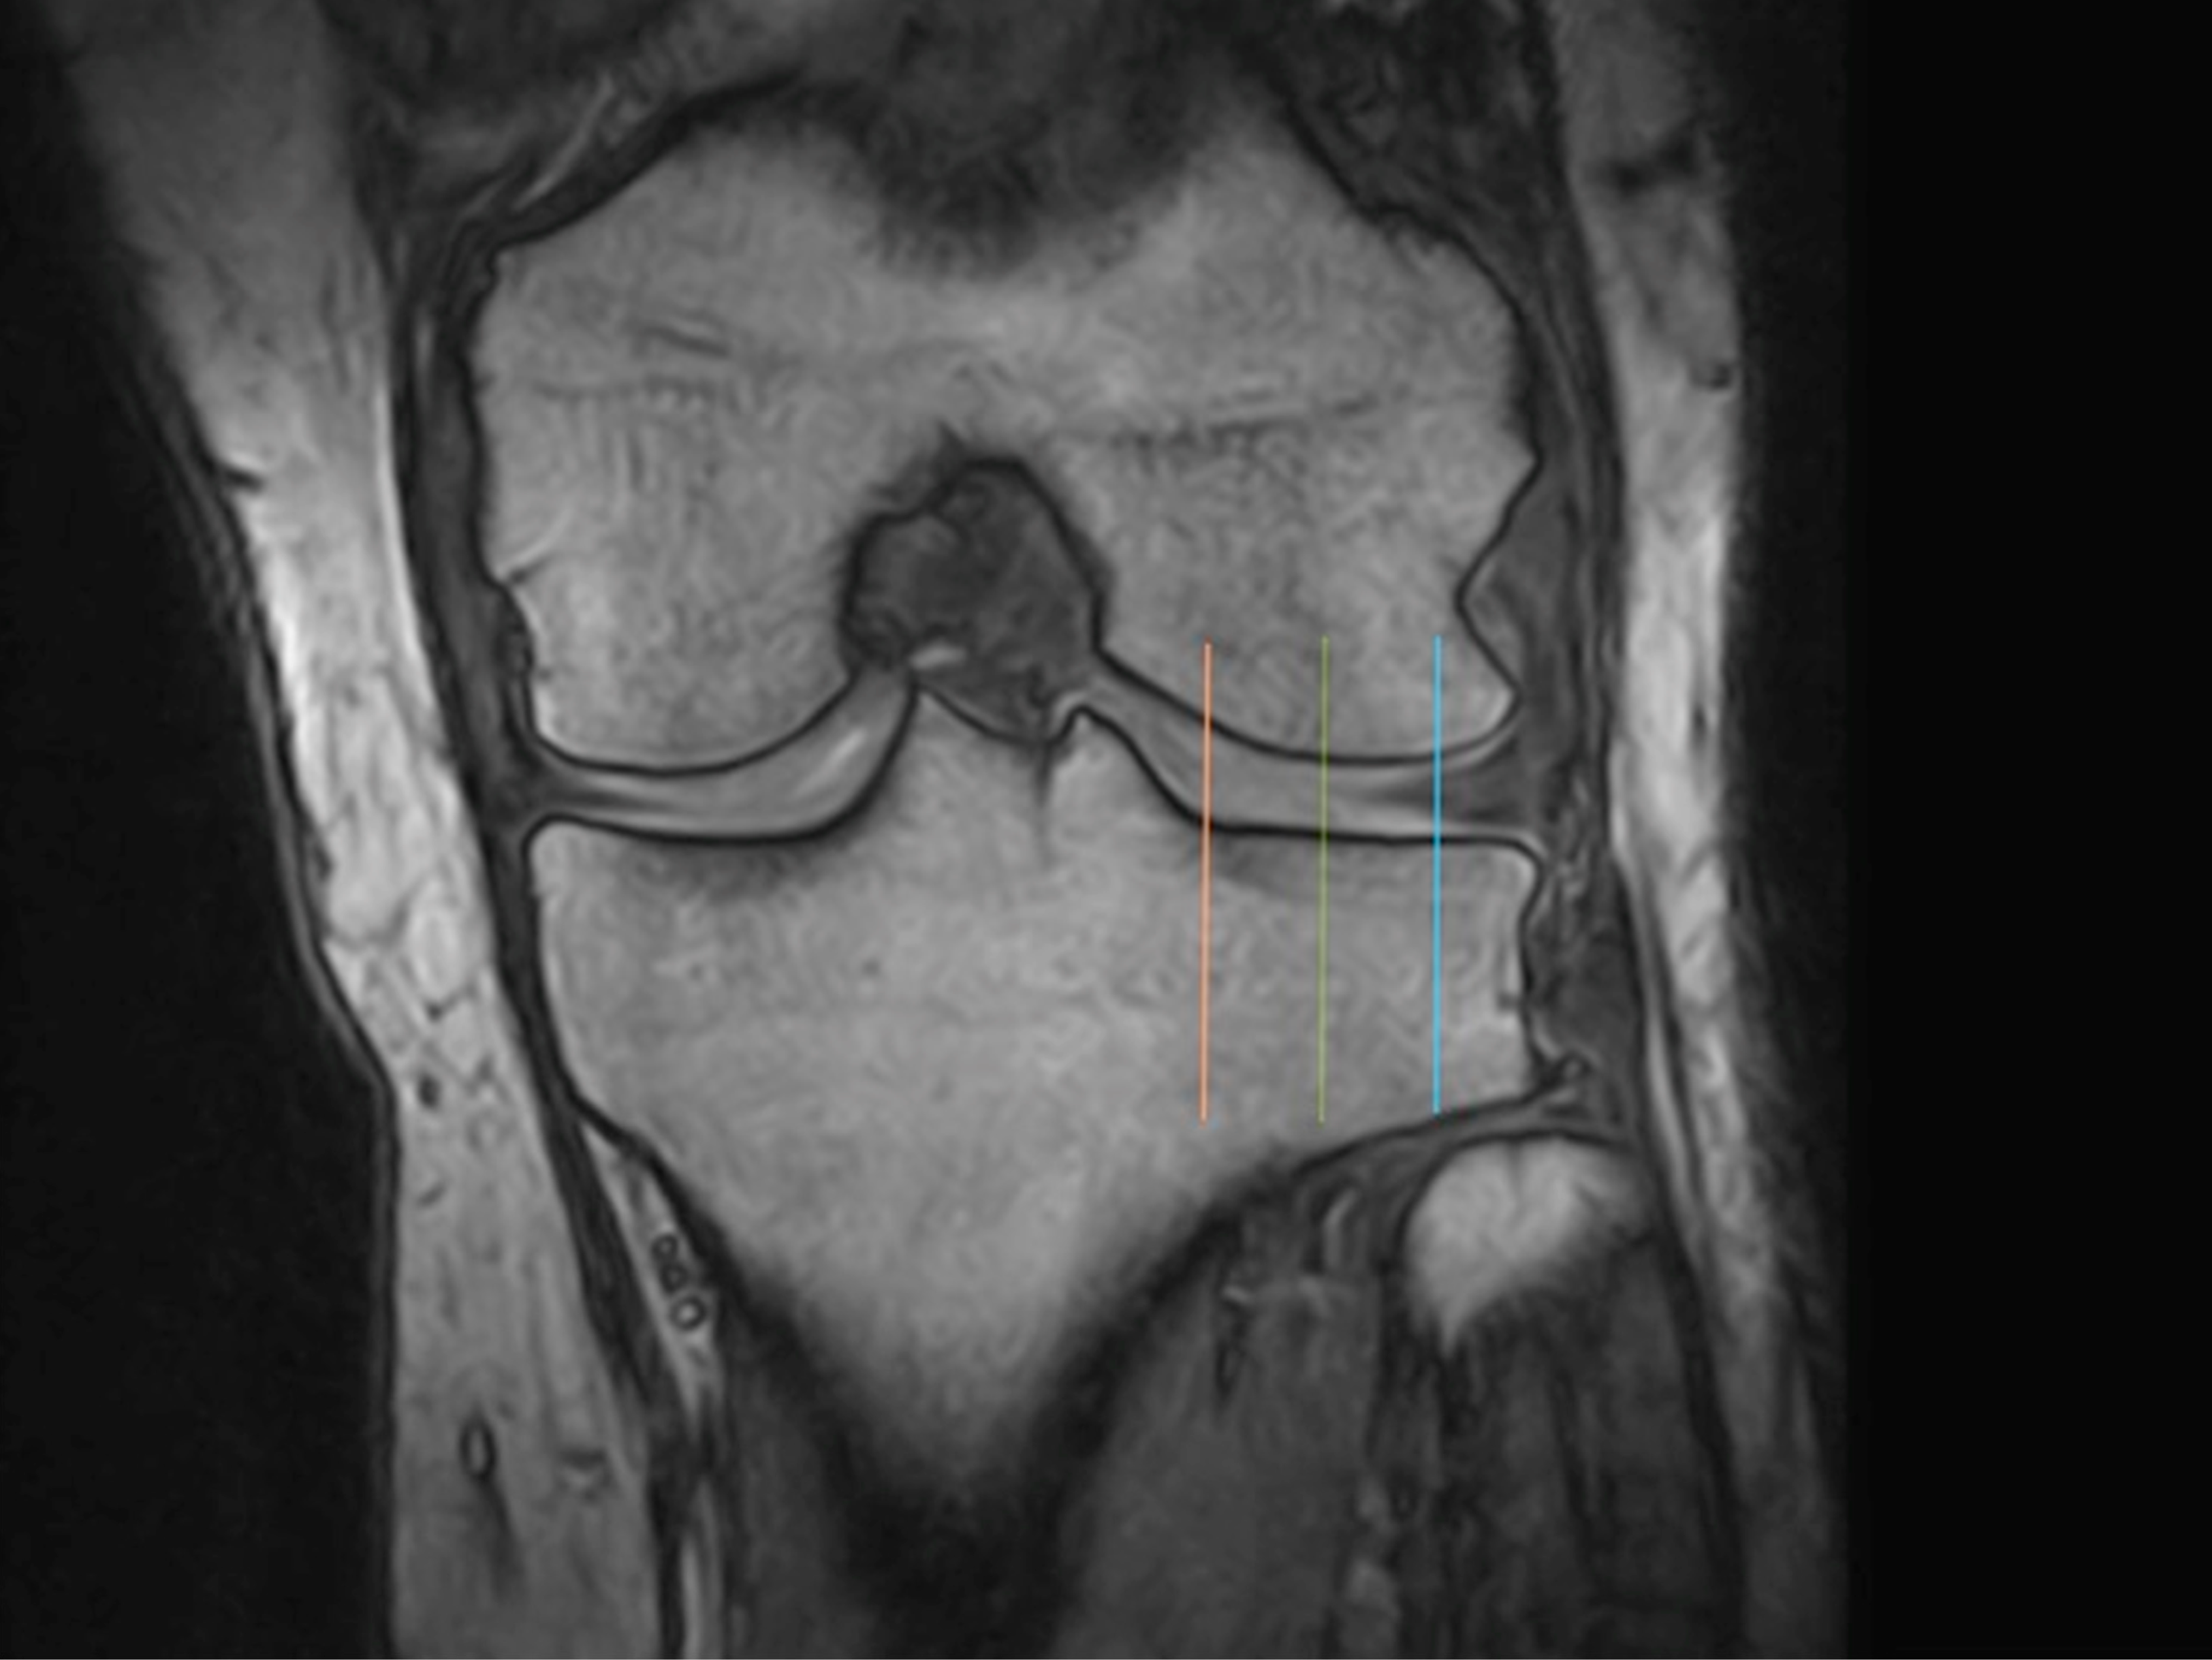

2.5. Evaluation of Knee Cartilage Thickness Using MRI

2.6. Medial and Lateral Femoral Condyle

2.7. Medial and Lateral Tibial Condyle